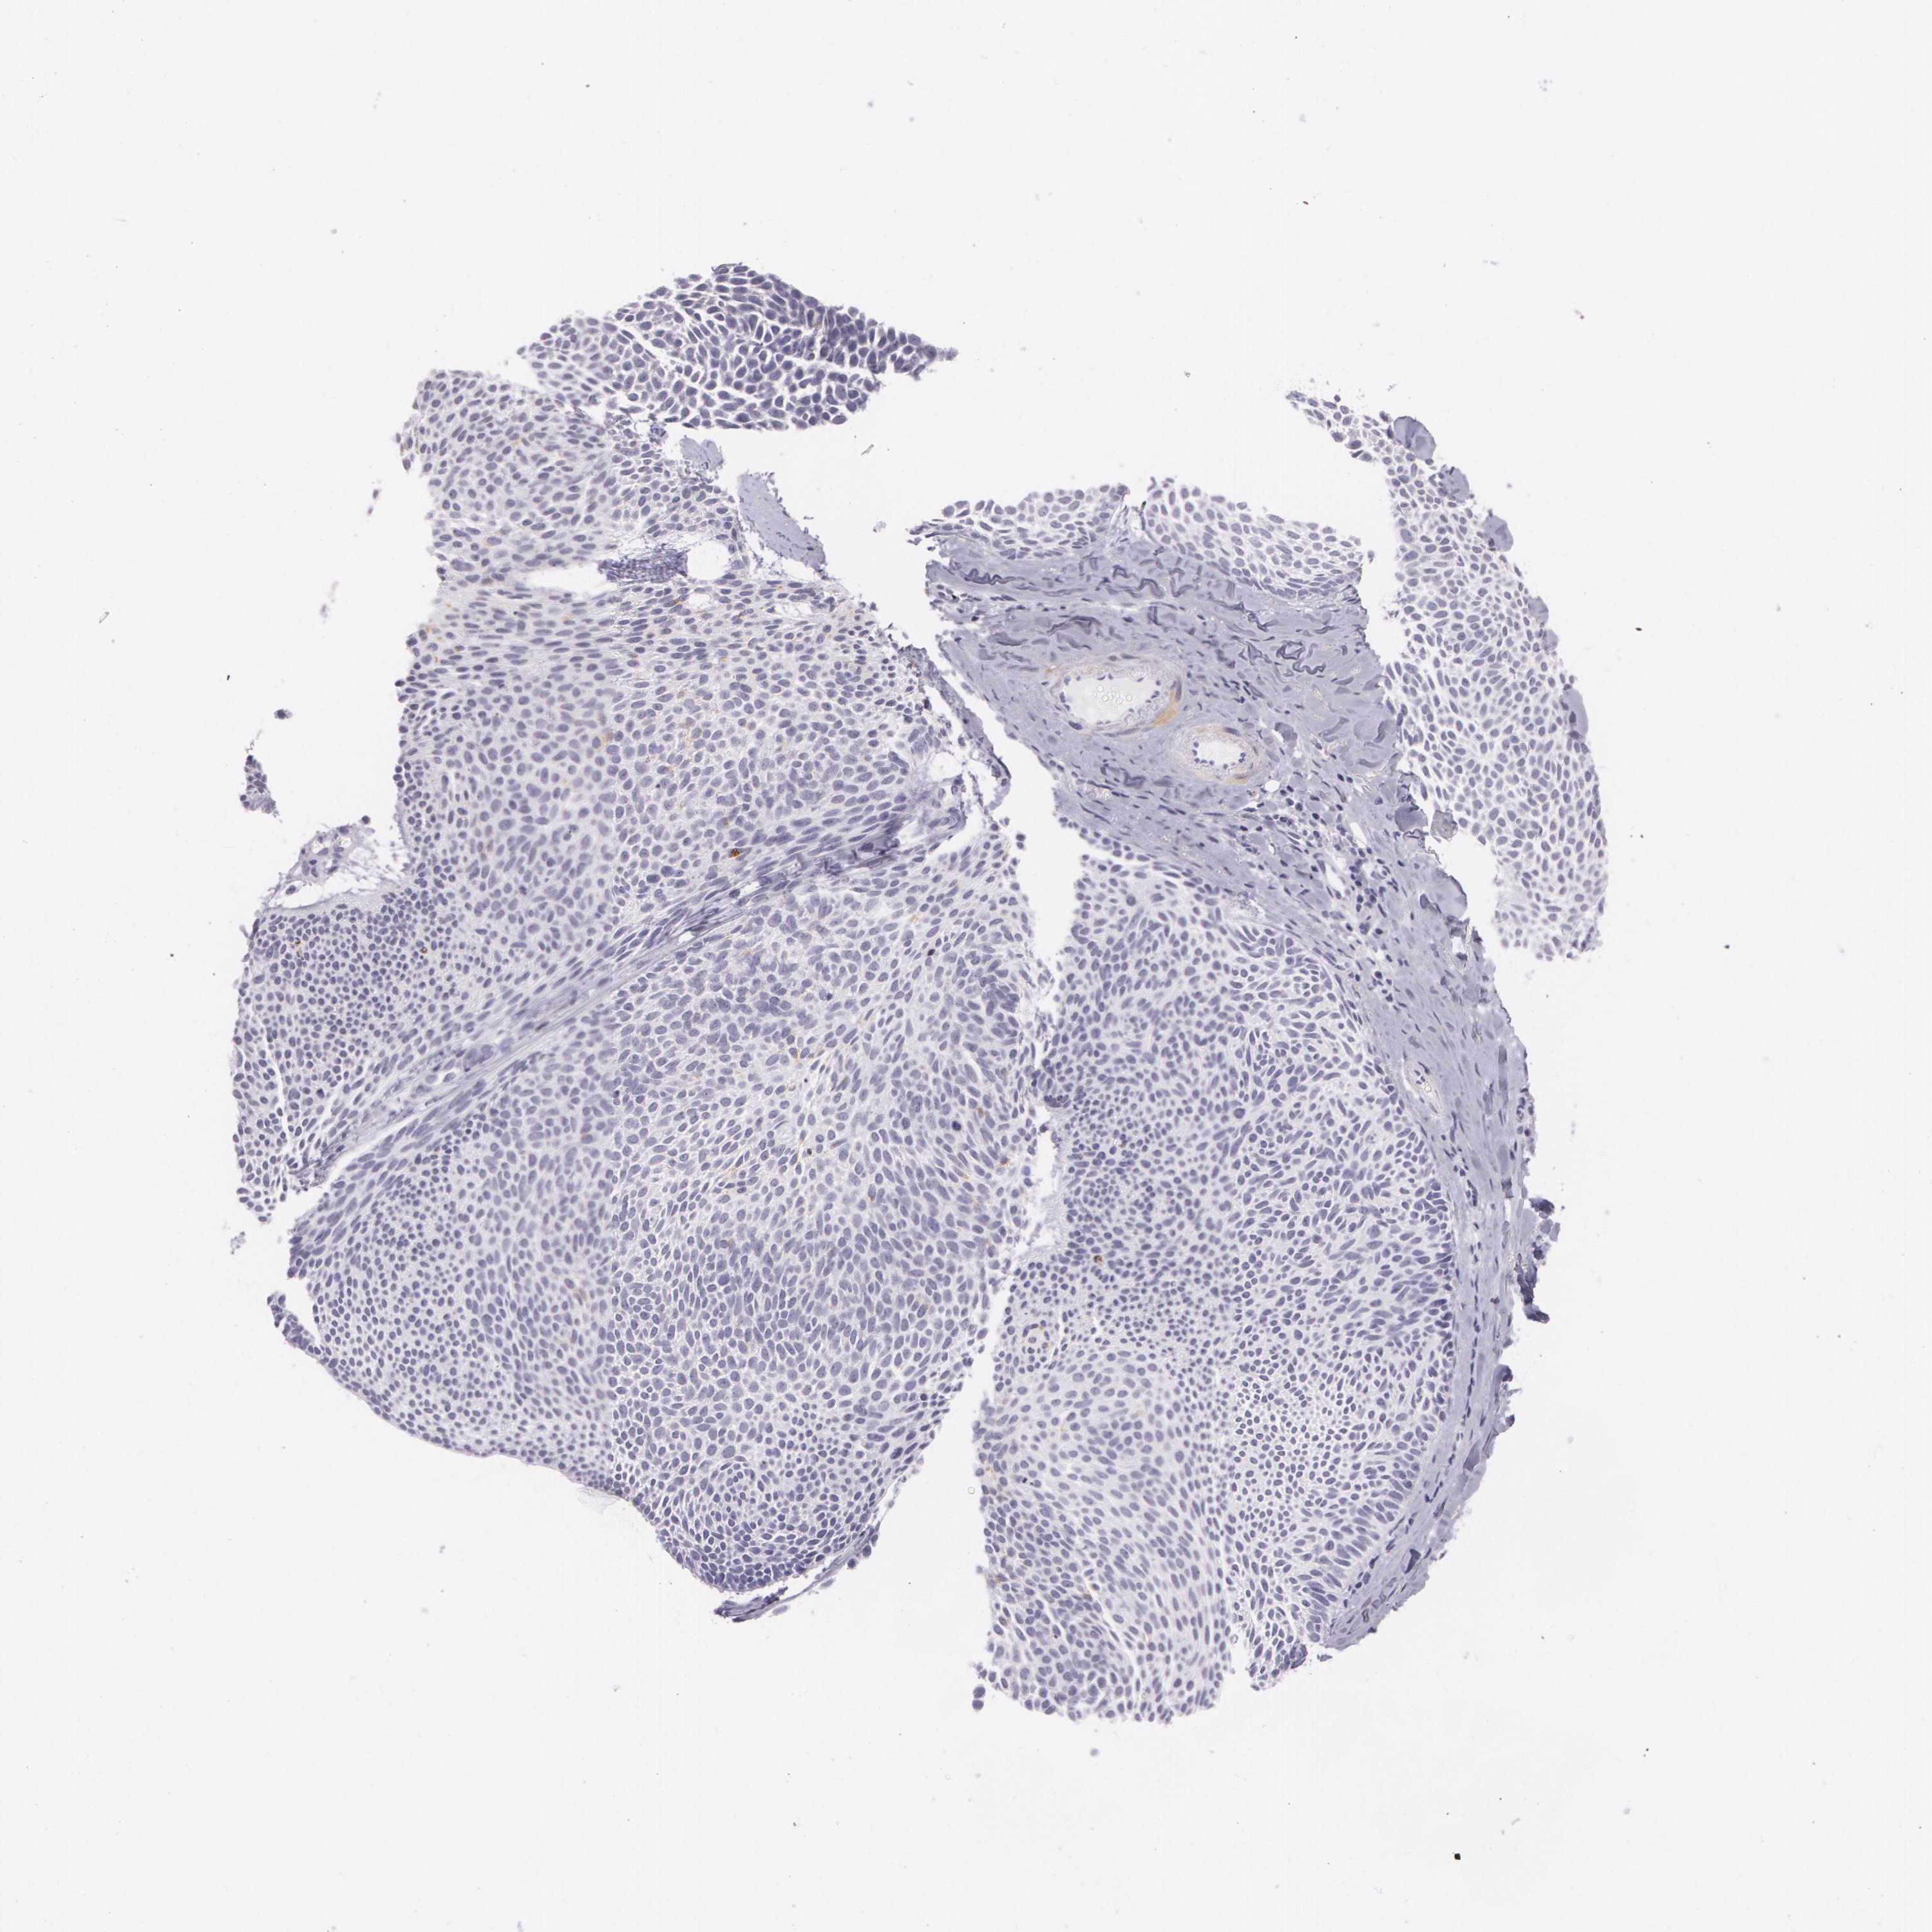

SKIN CANCER - Protein expressioni

A mouse-over function shows sample information and annotation data. Click on an image to view it in a full screen mode. Samples can be filtered based on level of antibody staining by selecting one or several of the following categories: high, medium, low and not detected. The assay and annotation is described here.

Each image is clickable and will lead to virtual microscopy that enables deeper exploration of all samples and also displays staining intensity scores, fraction scores and subcellular localization as well as patient and tissue information for each sample.

Antibody CAB040581

Staining

Low

Not detected

Intensity

Weak

Negative

Quantity

<25%

None

Location

Adnexal tumor, benign